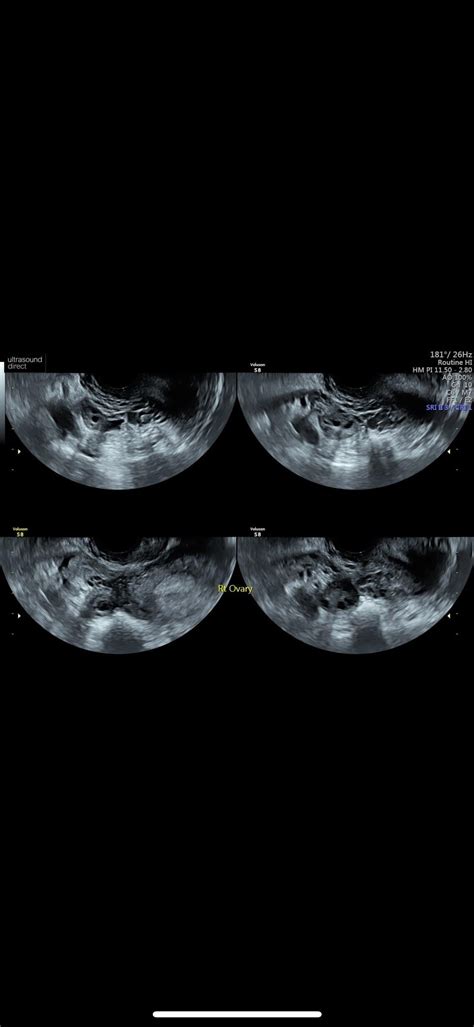

Okay, first things first, let’s talk about what the 20-week scan actually is. This isn’t just a fun sneak peek at your baby (though, let’s be honest, that’s a major perk!). The 20-week scan is a crucial medical appointment that provides a detailed look at your baby’s development. It’s a comprehensive ultrasound examination that typically takes place between 18 and 21 weeks of pregnancy. The main goal? To assess your baby’s physical development and identify any potential abnormalities. During the scan, the sonographer will check everything from the baby’s brain and spine to their heart, kidneys, and limbs. They’re essentially doing a full body check-up while your little one is still cozy inside! It’s also a chance to confirm the baby’s sex, if you want to know, and to check the position of the placenta. This scan is really thorough, and it’s designed to give you and your healthcare team as much information as possible about your baby’s health. Now, I know, hearing about all the things they check can sound a bit scary, but remember, the vast majority of scans come back with good news. Think of it as a super-detailed health check to ensure everything is progressing as it should. It’s a proactive step in ensuring the well-being of both you and your baby.

Now, let’s tackle the elephant in the room: the potential for bad news. It’s completely normal to worry about this, and many expectant parents find themselves searching online for information and experiences. Forums like OSCIPSEC, HowSc, and Reddit can be both a blessing and a curse. On one hand, they offer a sense of community and shared experiences; you can connect with others who are going through the same thing. On the other hand, they can also be a breeding ground for anxiety, as you might come across stories that are particularly worrisome. So, what kind of issues can be detected at a 20-week scan? Well, sonographers are looking for a range of potential problems, from minor issues that may resolve on their own to more serious conditions that require further investigation and intervention. These can include structural abnormalities, such as heart defects, spina bifida, or cleft lip and palate. They also check for markers that could indicate chromosomal abnormalities, such as Down syndrome. It’s important to understand that finding a marker doesn’t necessarily mean there’s a problem; it just means that further testing might be recommended. Sometimes, the scan might reveal issues with the placenta or amniotic fluid levels, which can affect the baby’s growth and development. In some cases, the sonographer might not be able to get a clear view of certain structures, which could lead to a repeat scan being scheduled. This doesn’t always mean something is wrong; it could just be the baby’s position or other factors. Remember, while it’s good to be informed, try not to jump to conclusions based on what you read online. Every pregnancy is unique, and the best source of information is always your healthcare provider. They can provide personalized advice and support based on your specific situation.